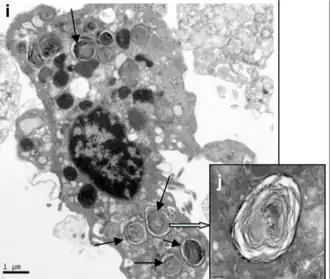

Type II-pneumocyten (granulaire pneumocyten) in de wand van de longblaasjes bevatten secretoire organellen die bekend staan als lamellaire lichamen of lamellaire korrels, die fuseren met de celmembranen en een oppervlakte-actieve stof afscheiden. Deze stof is een film van vette substanties, een groep fosfolipiden die de oppervlaktespanning van de longblaasjes verlagen. De fosfolipiden worden opgeslagen in de lamellaire lichamen. Zonder deze coating zouden de longblaasjes instorten. De oppervlakte-actieve stof wordt continu vrijgegeven door exocytose. Het opnieuw opblazen van de longblaasjes na uitademing wordt gemakkelijker gemaakt door de oppervlakte-actieve stof, die de oppervlaktespanning in de dunne vloeibare coating van de longblaasjes vermindert. De vloeibare coating wordt door het lamellaire lichaam geproduceerd om de overdracht van gassen tussen bloed en longblaasjeslucht te vergemakkelijken, en de type II-pneumocyten bevinden zich doorgaans in de bloed-luchtbarrière.[8][9] Lamellaire lichaampjes zijn osmofiele cellichaampjes met een concentrische lamellaire structuur en worden gevormd in het golgicomplex.